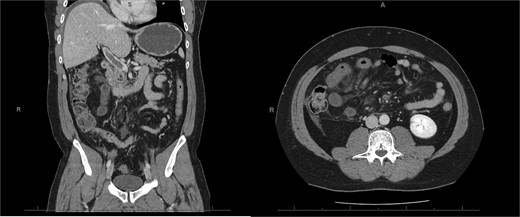

A 45-year-old male presenting with a 10-day history of isolated right lower quadrant (RLQ) abdominal pain. His history included deep vein thrombosis, coronary artery disease with prior STEMI, left anterior descending artery stenting in 2014, and ongoing antiplatelet therapy with aspirin. Upon admission, RLG tenderness was noted. Laboratory revealed leucocytosis (WBC 16 G/L) and elevated CRP (70 mg/L). E-CT revealed superior mesenteric and portal systems thrombosis with ischemia of a small bowel loop in the RLQ, characterized by absent bowel wall enhancement and free fluid (Fig. 4). Besides these findings, he was managed conservatively with a UFH bolus of 5000 U/l, followed by a continuous infusion of 36 000 U/l over 24 h (target INR 0. 35–0. 7), Ceftriaxone and Metronidazole, bowel rest, and ICU monitoring for 48 h. Clinical and biological improvement was rapid. E-CT on the second day showed no signs of perforation (Fig. 5). He was discharged after 7 days on LMWH (enoxaparin sodium 90 mg every 12 h). Twenty days later, he re-presented with acute RLQ pain and localized peritonism. E-CT revealed a covered perforation of the previously ischemic small bowel loop (Fig. 6). A segmental bowel resection with primary anastomosis was performed by laparotomy (Fig. 7). The postoperative course was uneventful, and he was discharged on postoperative day 4 with sodium enoxaparin 90 mg/12 h.

E-CT of the second patient 48 h after conservative management, showing no further complications, including no signs of perforation regarding the bowel wall located with dashed arrows.